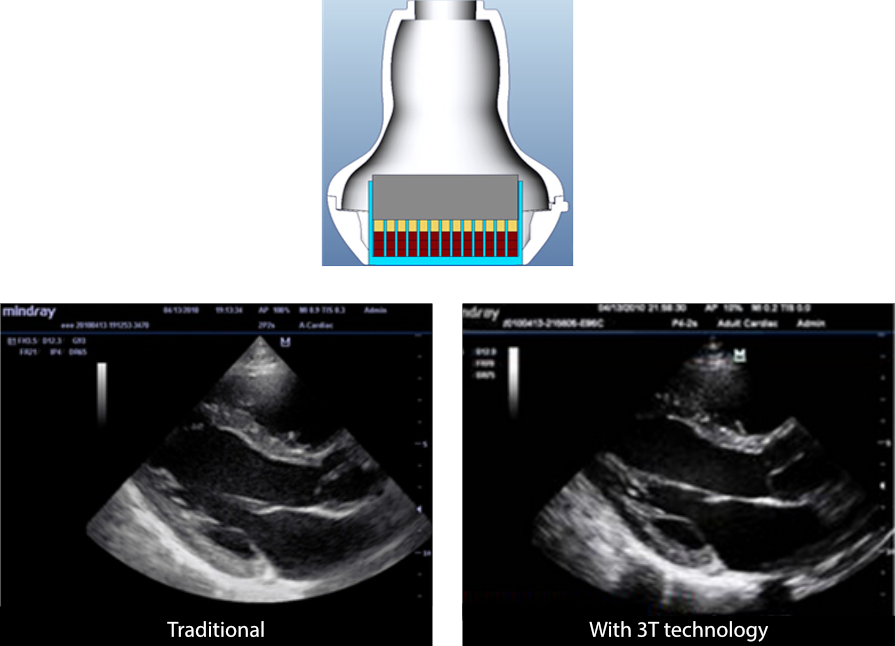

3T Transducer Technology?

La tecnologia trasduttori brevettata Mindray incrementa la larghezza d'onda delle immagini e l'efficienza della trasmissione.

┬Ę Design strato triple-match per una maggiore sensibilit├Ā, larghezza di banda e S/N migliorato

┬Ę Design con separazione totale degli elementi della sonda per ridurre i rumori di interferenza, migliore direttivit├Ā e risoluzione laterale potenziata

┬Ę Design con controllo termico per una migliore trasmissione acustica